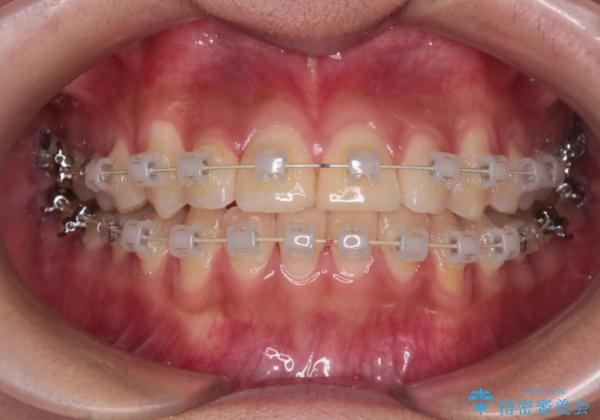

抜かない矯正 審美装置によるワイヤー治療

- 前歯のガタガタを主訴に来院されました。

インビザラインも提案しましたが、装着時間を確実に確保できるか不安ということもありワイヤー矯正を希望されました。

装着時間に不安がある人は、ワイヤー矯正をおすすめしております。短期間で治療でき患者様にも満足していただきました。